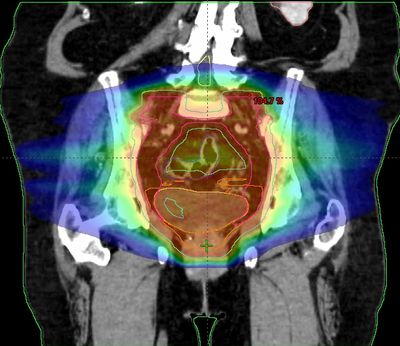

Clinical technologists (also known as healthcare science practitioners) are responsible for planning an individual patient’s treatment, using complex computer algorithms.

As a Clinical Technologist you will be involved in: